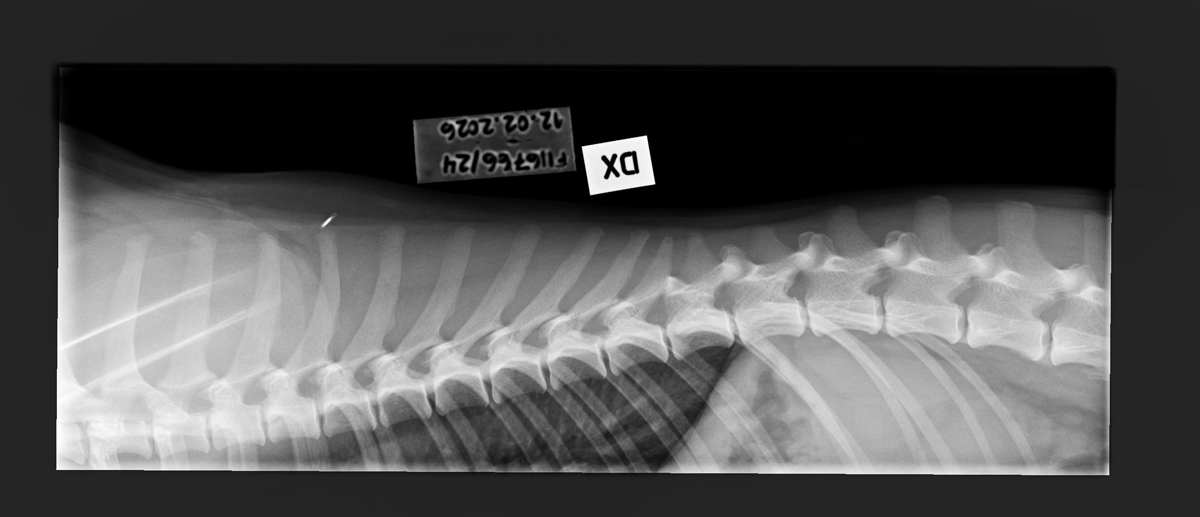

- Finnish Kennel Club's elbow x-ray report Dec '25: Signs suggestive of medial coronoid disease; further information about the condition of the joints can be obtained, if necessary, by computed tomography (CT) examination

- Finnish Kennel Club's elbow CT report Feb '26: A small amount of new bone formation around the medial coronoid process of the left elbow

- Free of lumbosacral transitional vertebrae (LTV0)

- Free of spondylosis (SP0)

- Free of vertebral anomalies (VA0)

- Spine x-rays: 1, 2 ja 3